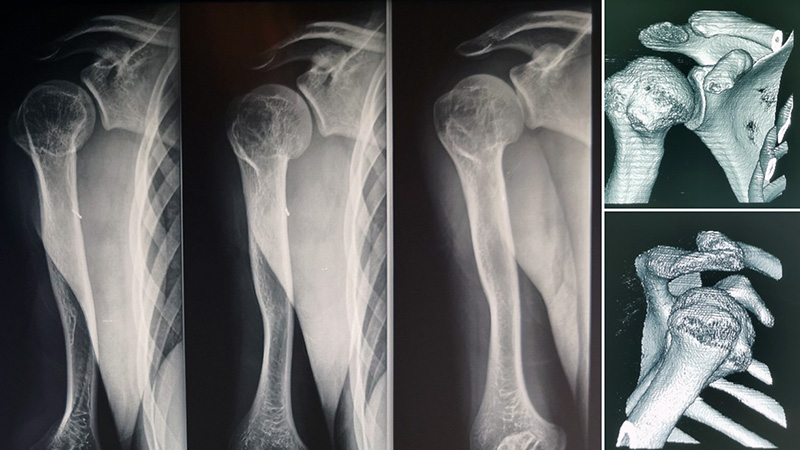

Un trauma all’età di sei anni ha compromesso la cartilagine di accrescimento dell’omero in un giovane paziente, causando una progressiva discrepanza di 8,5 cm nella lunghezza dell’arto al raggiungimento dell’età adulta. L’evento traumatico, inizialmente trattato come una frattura, ha avuto conseguenze a lungo termine sul normale sviluppo osseo.

Con il team Kirienko, abbiamo eseguito con successo un’osteotomia dell’omero con applicazione di fissatore esterno tipo Ilizarov. Questo approccio ha permesso di ottenere un allungamento progressivo e controllato dell’osso.